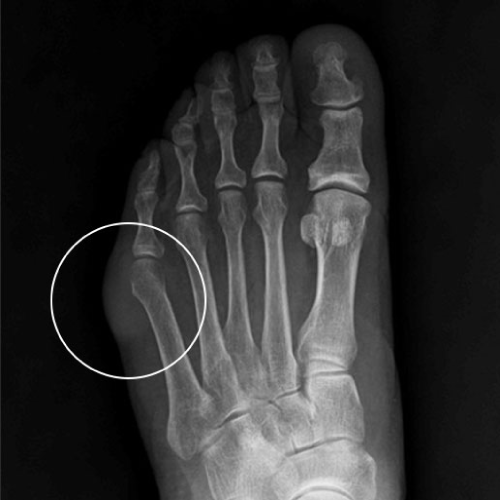

소건막류

소건막류는 새끼발가락 뿌리 관절이 엄지발가락 쪽으로 휘게 되면서 새끼발가락 부분이 돌출되어 신발에 닿거나 설 때 통증이 발생하는 질환 입니다.

엄지발가락 부분이 튀어나오는 무지외반과 동반되는 경우가 많습니다.

소건막류 증상

□ 외관상으로 새끼발가락 쪽이 돌출되어 있음

□ 새끼발가락 쪽이 양반다리를 하면 아프다

□ 신발을 신으면 자극이 되어 새끼발가락 쪽 통증을 느낌

□ 새끼발가락 돌출 부위가 붉게 변하고 굳은살이 생김